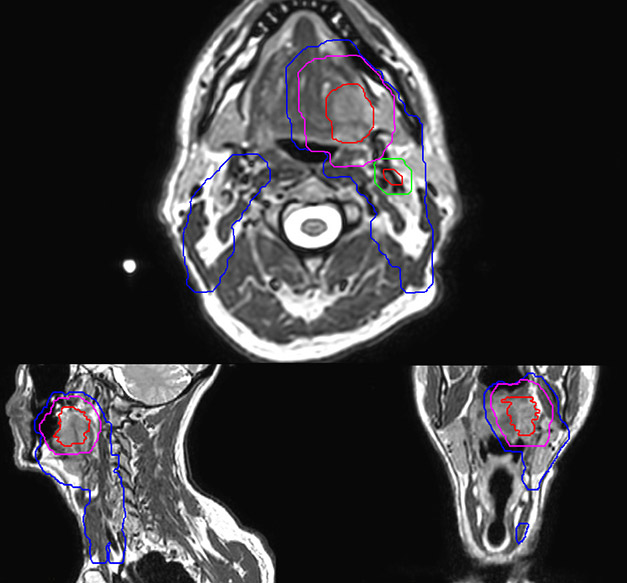

Epidermoid carcinoma of the left tongue base

The patient was diagnosed with an epidermoid carcinoma of the base of the left invading the amygdala lodge and the amygdaloglossal groove. Radiochemotherapy with curative aim was prescribed with a dose of 70 Gy for the tumor, 66 Gy on the suspicious nodes and 56 Gy on the elective drainage areas - in 33 fractions.

Personalized VMAT dose planned in Philips Pinnacle.